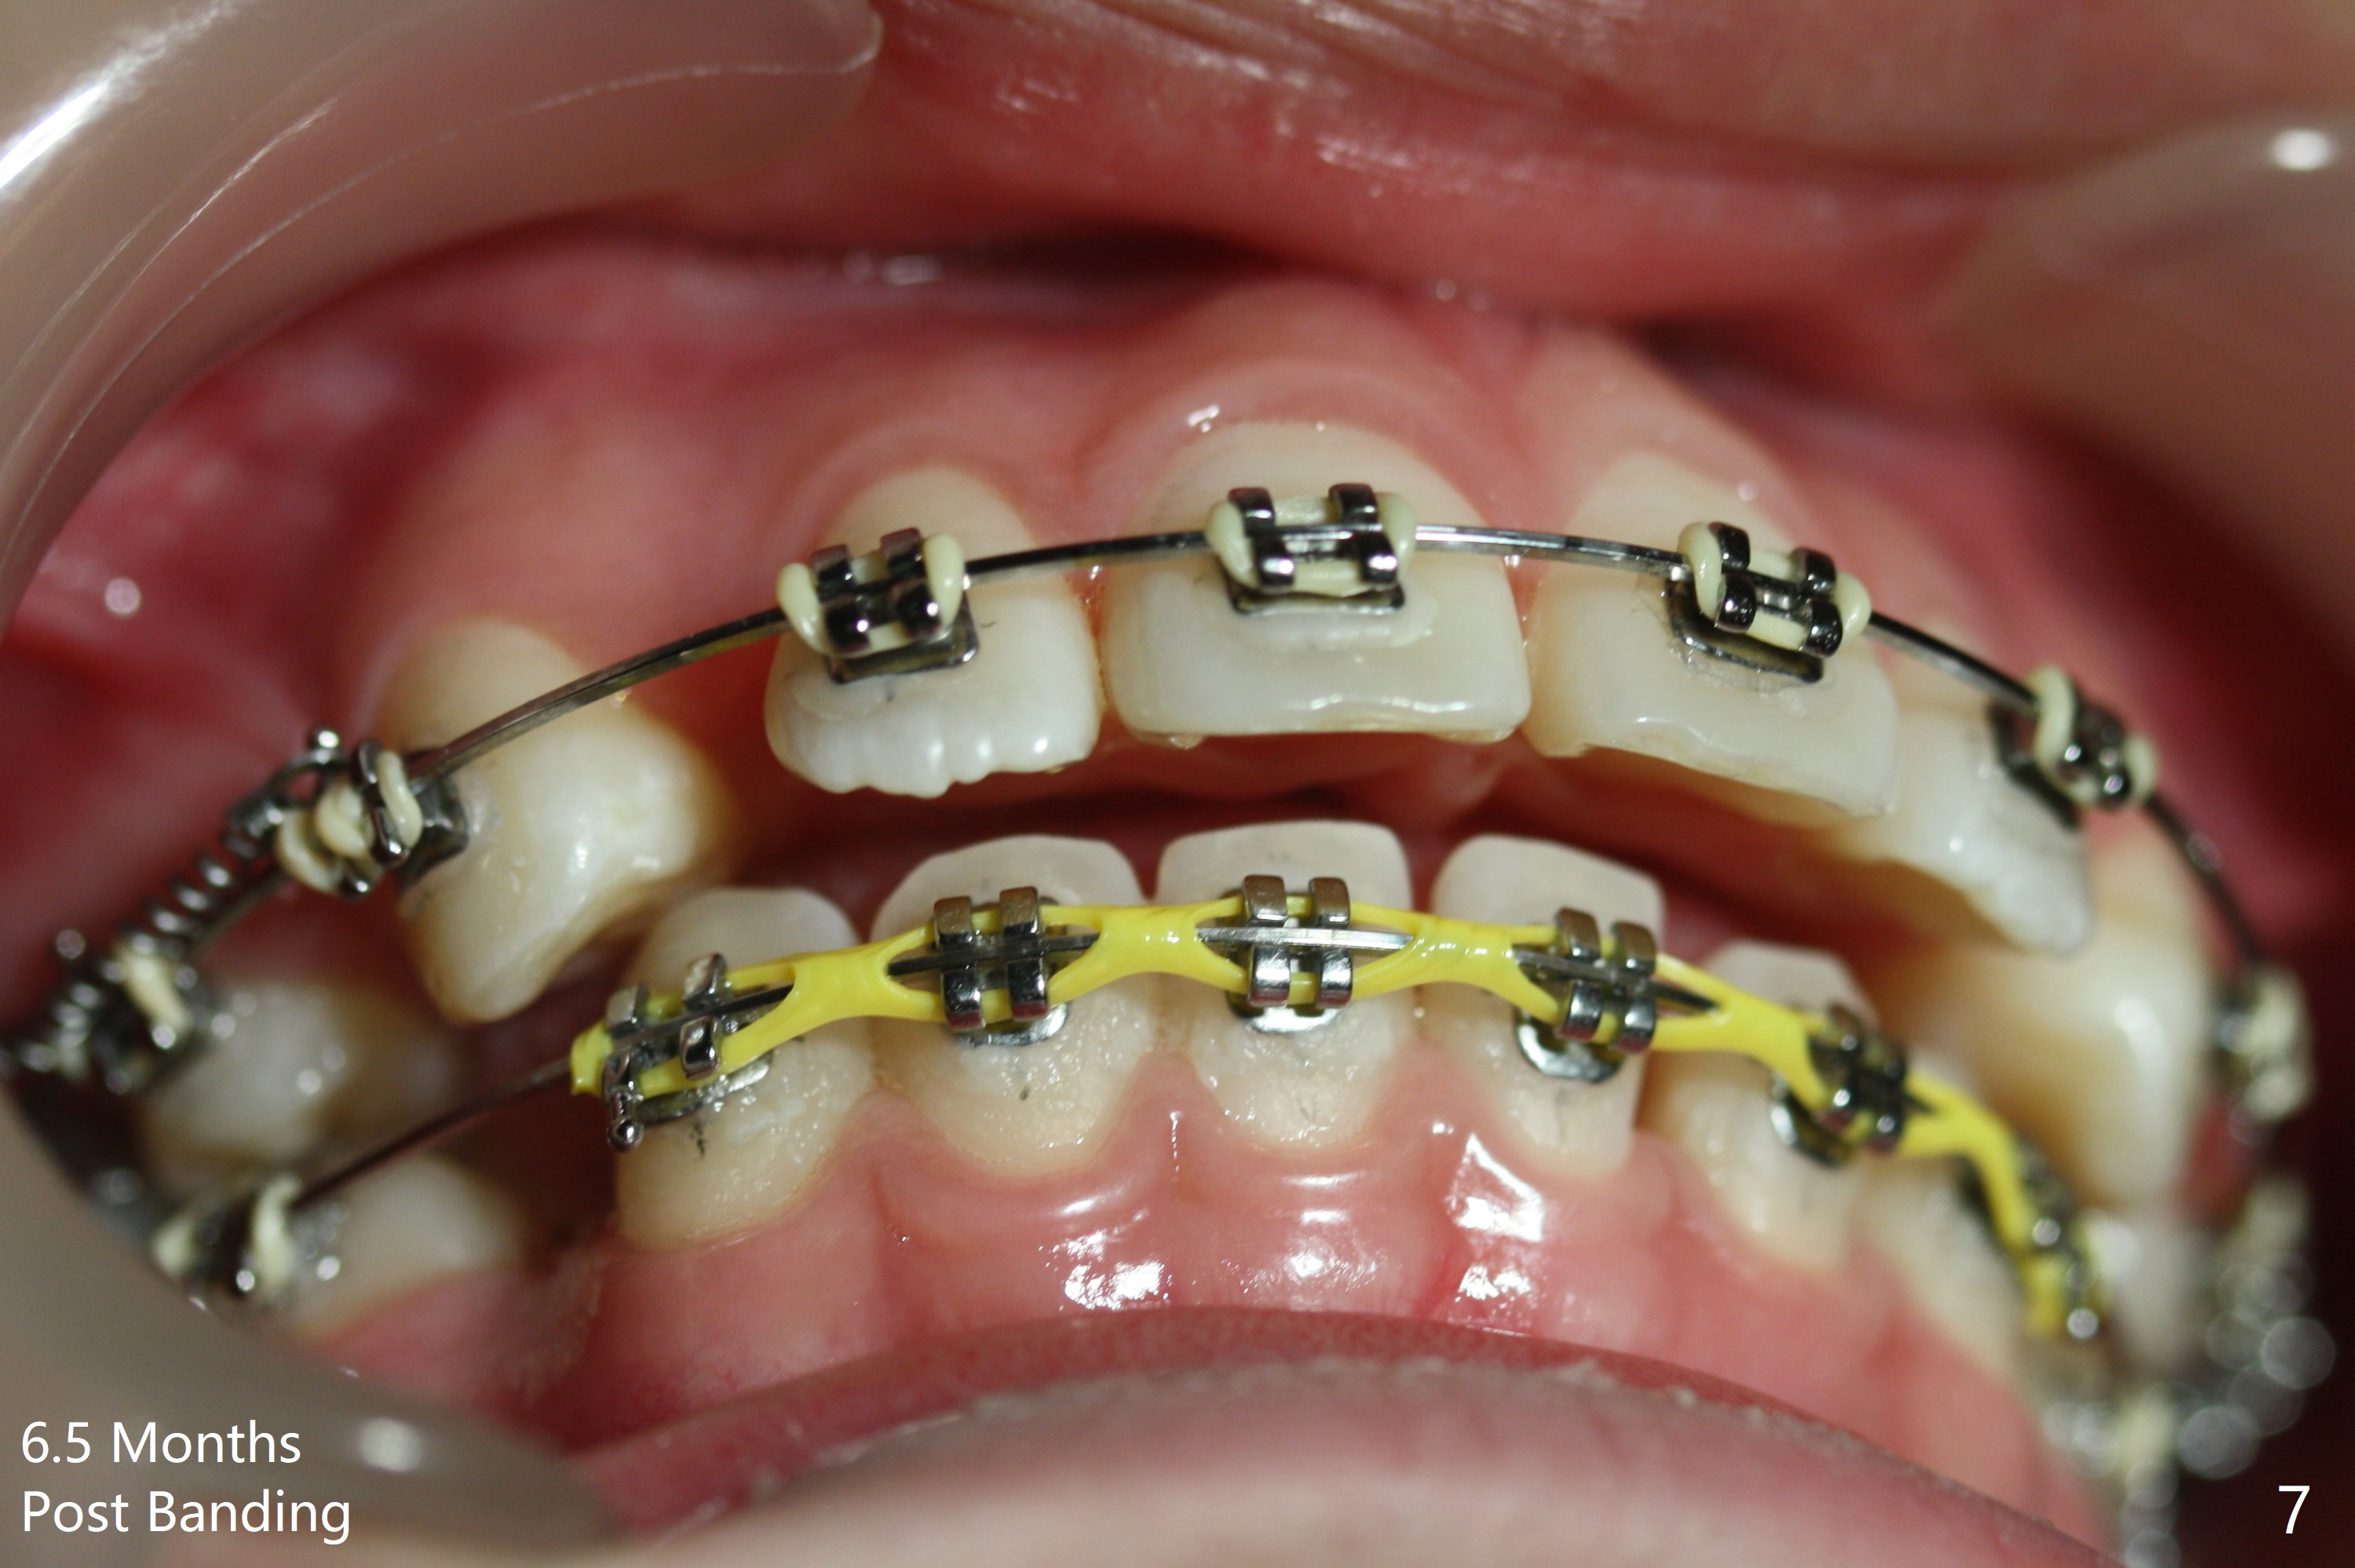

Two weeks post extraction of 4 bicuspids, brackets and bands are placed in 20 teeth (Fig.1-3, 14 niti). No bands are placed at 7s because of short crowns and tight contacts. When 16x16 wires are used, start Class II retraction. The latter is initiated with elastics when 18 ss wires are placed (Fig.4,5). U3s have been distalized with closed springs for 3 months (Fig.6,7). U2s are close to distalization 13 months post banding, 3.5 months post posted wire (Fig,8,9) with overjet (Fig.10). Class II retraction is re-initiated. When the upper incisors are retracted, the anterior overjet remains large. It appears that U6s have been retracted anterior, as indicated by the space between U6/7 (Fig.11), because of no use of U7s as anchors. Brackets are just placed with 18 niti arch wire. They will be retracted distal using the rest of the upper teeth and lower teeth (using Class II retraction) as anchor. There is root resorption of the upper anteriors 2 years 1 month post banding (Fig.12,13).